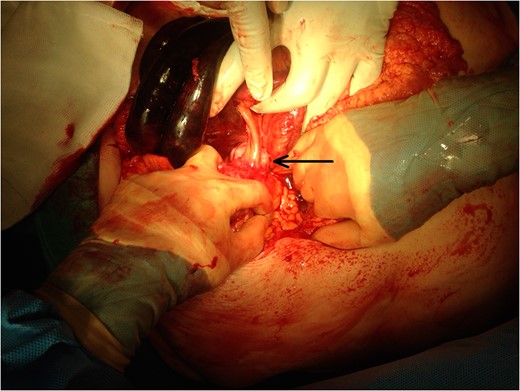

A 74-year-old female, with a background history of hypertension and hypothyroidism, presented to the emergency department with a 6-h history of sudden onset generalized abdominal pain. The pain was colicky in nature, associated with nausea and refractory to analgesia. Examination revealed tenderness in the right upper quadrant and epigastrium. Blood tests were normal except for a mild neutrophilia (7.5 × 109/l) and lactate of 2.5 mmol/l. A computed tomography (CT) scan of her abdomen and pelvis was performed which showed abnormal loops of small bowel along the right side of the abdomen with mesenteric fat stranding. A partially calcified structure was noted lying medial to the loops of bowel (Figs 1 and 2). The patient proceeded to have an explorative laparotomy performed. Intraoperative findings revealed an ischaemic loop of small bowel wrapped around a mass in the mesentery adjacent to the sigmoid colon (Fig. 3). The patient underwent a partial small bowel resection with primary anastomosis and en-bloc resection of the mass with the formation of an end colostomy. The final histological revealed a 6 × 4 × 4 cm cystic colonic duplication cyst separate but adjacent to the sigmoid colon. The inner lining of the cyst revealed mucinous epithelium, with mucin contained within. The wall of the cyst was sclerotic with occasional lymphoid aggregates, smooth muscle and neurovascular bundles (Fig. 4). The patient made a good recovery and was discharged home.

Intraoperative image black arrow pointing to intra-abdominal calcified structure. Ischaemic bowel in top left of image.